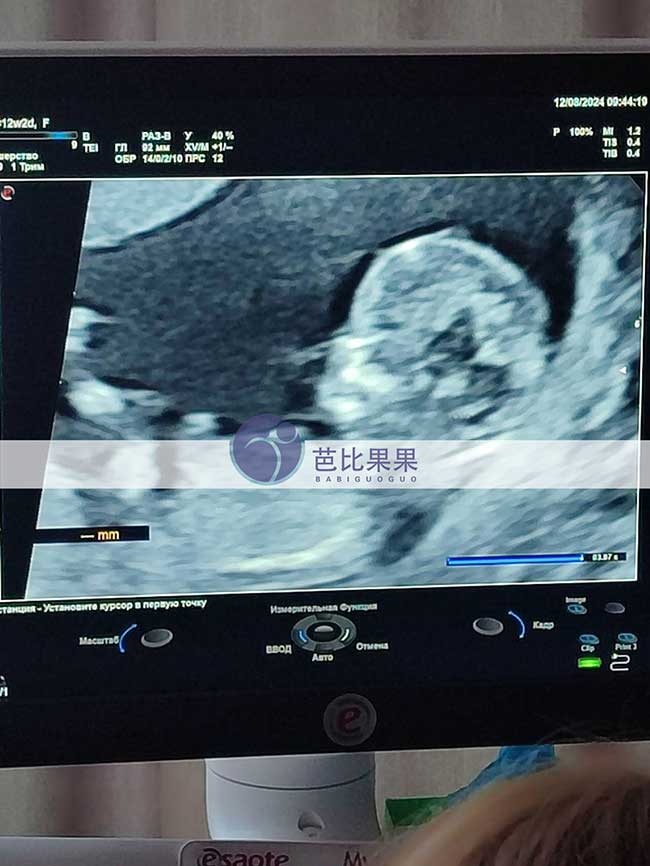

C女士在乌克兰DY匹配的试管妈妈来做孕12周的B超

C女士在乌克兰DY匹配的试管妈妈来做孕12周的B超啦,试管妈妈美美的,双胞胎宝宝也发育的很好